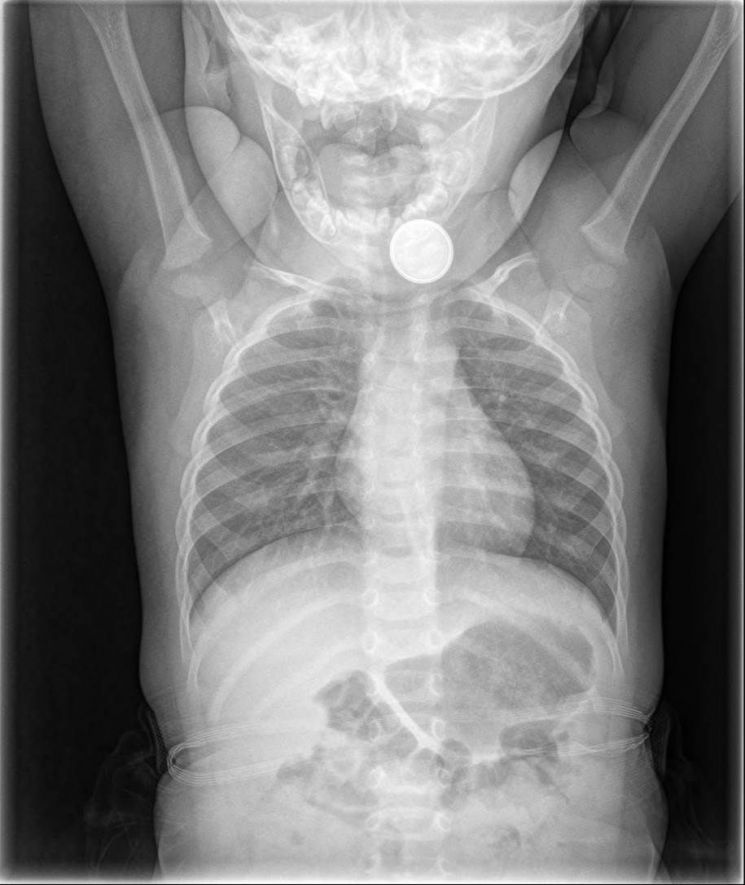

아이가 건전지를 삼킨 걸 알게 된 가족들은 곧바로 병원을 찾았고, X-레이 검사 결과 식도에 건전지가 낀 것이 확인됐다.

소년의 식도에서 나온 동전형 건전지(왼쪽) [사진출처= 리버풀에코]